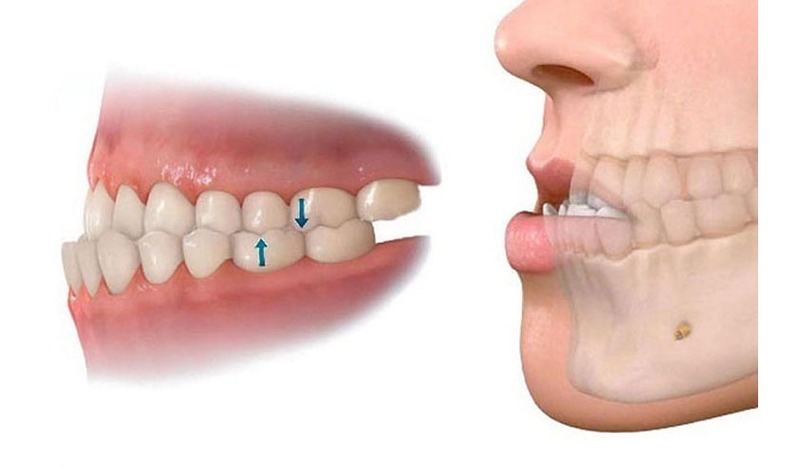

Răng hô, vẩu

Tình trạng răng hô khiến gương mặt trở nên kém hài hòa, đồng thời tiềm ẩn nguy cơ gặp phải những vấn đề khác như: khó khăn trong ăn uống, sai lệch khớp cắn hoặc làm mất cân đối các đường nét khuôn mặt. Phương pháp niềng răng trong suốt giúp khắc phục tình trạng này hiệu quả, đưa hàm răng trên lùi vào đúng vị trí, răng trở nên đều và đẹp hơn.

Răng móm (khớp cắn ngược)

Răng móm là tình trạng xương hàm dưới đưa ra ngoài so với hàm trên, tạo nên khớp cắn ngược, gây ảnh hưởng nghiêm trọng đến tính thẩm mỹ khuôn mặt cũng như chức năng ăn nhai. Trong những trường hợp răng móm ở mức độ vừa phải, niềng răng trong suốt là giải pháp hữu ích giúp dịch chuyển răng dần về đúng vị trí, cải thiện đáng kể khả năng nhai và vẻ ngoài khuôn mặt.